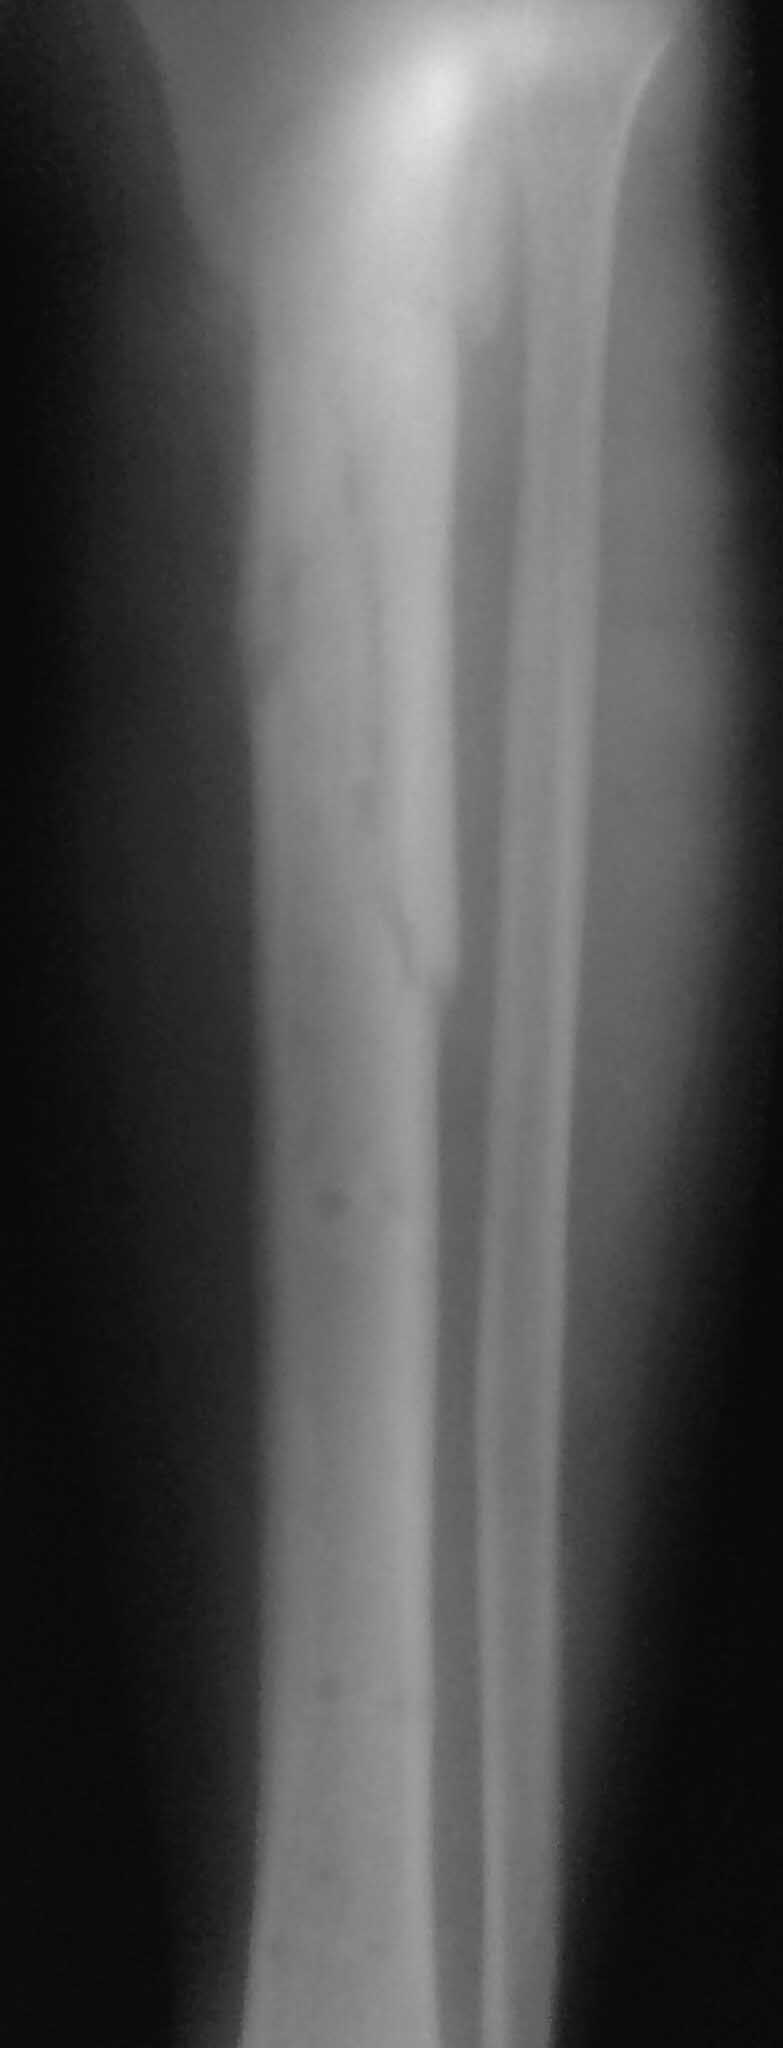

Спасибо за обсуждение.Отправил остальные R, изиняюсь за качество.

3.Перелом на 2 уровнях, есть искривление костно-мозгового канала. Проксимальный отломок короткий.